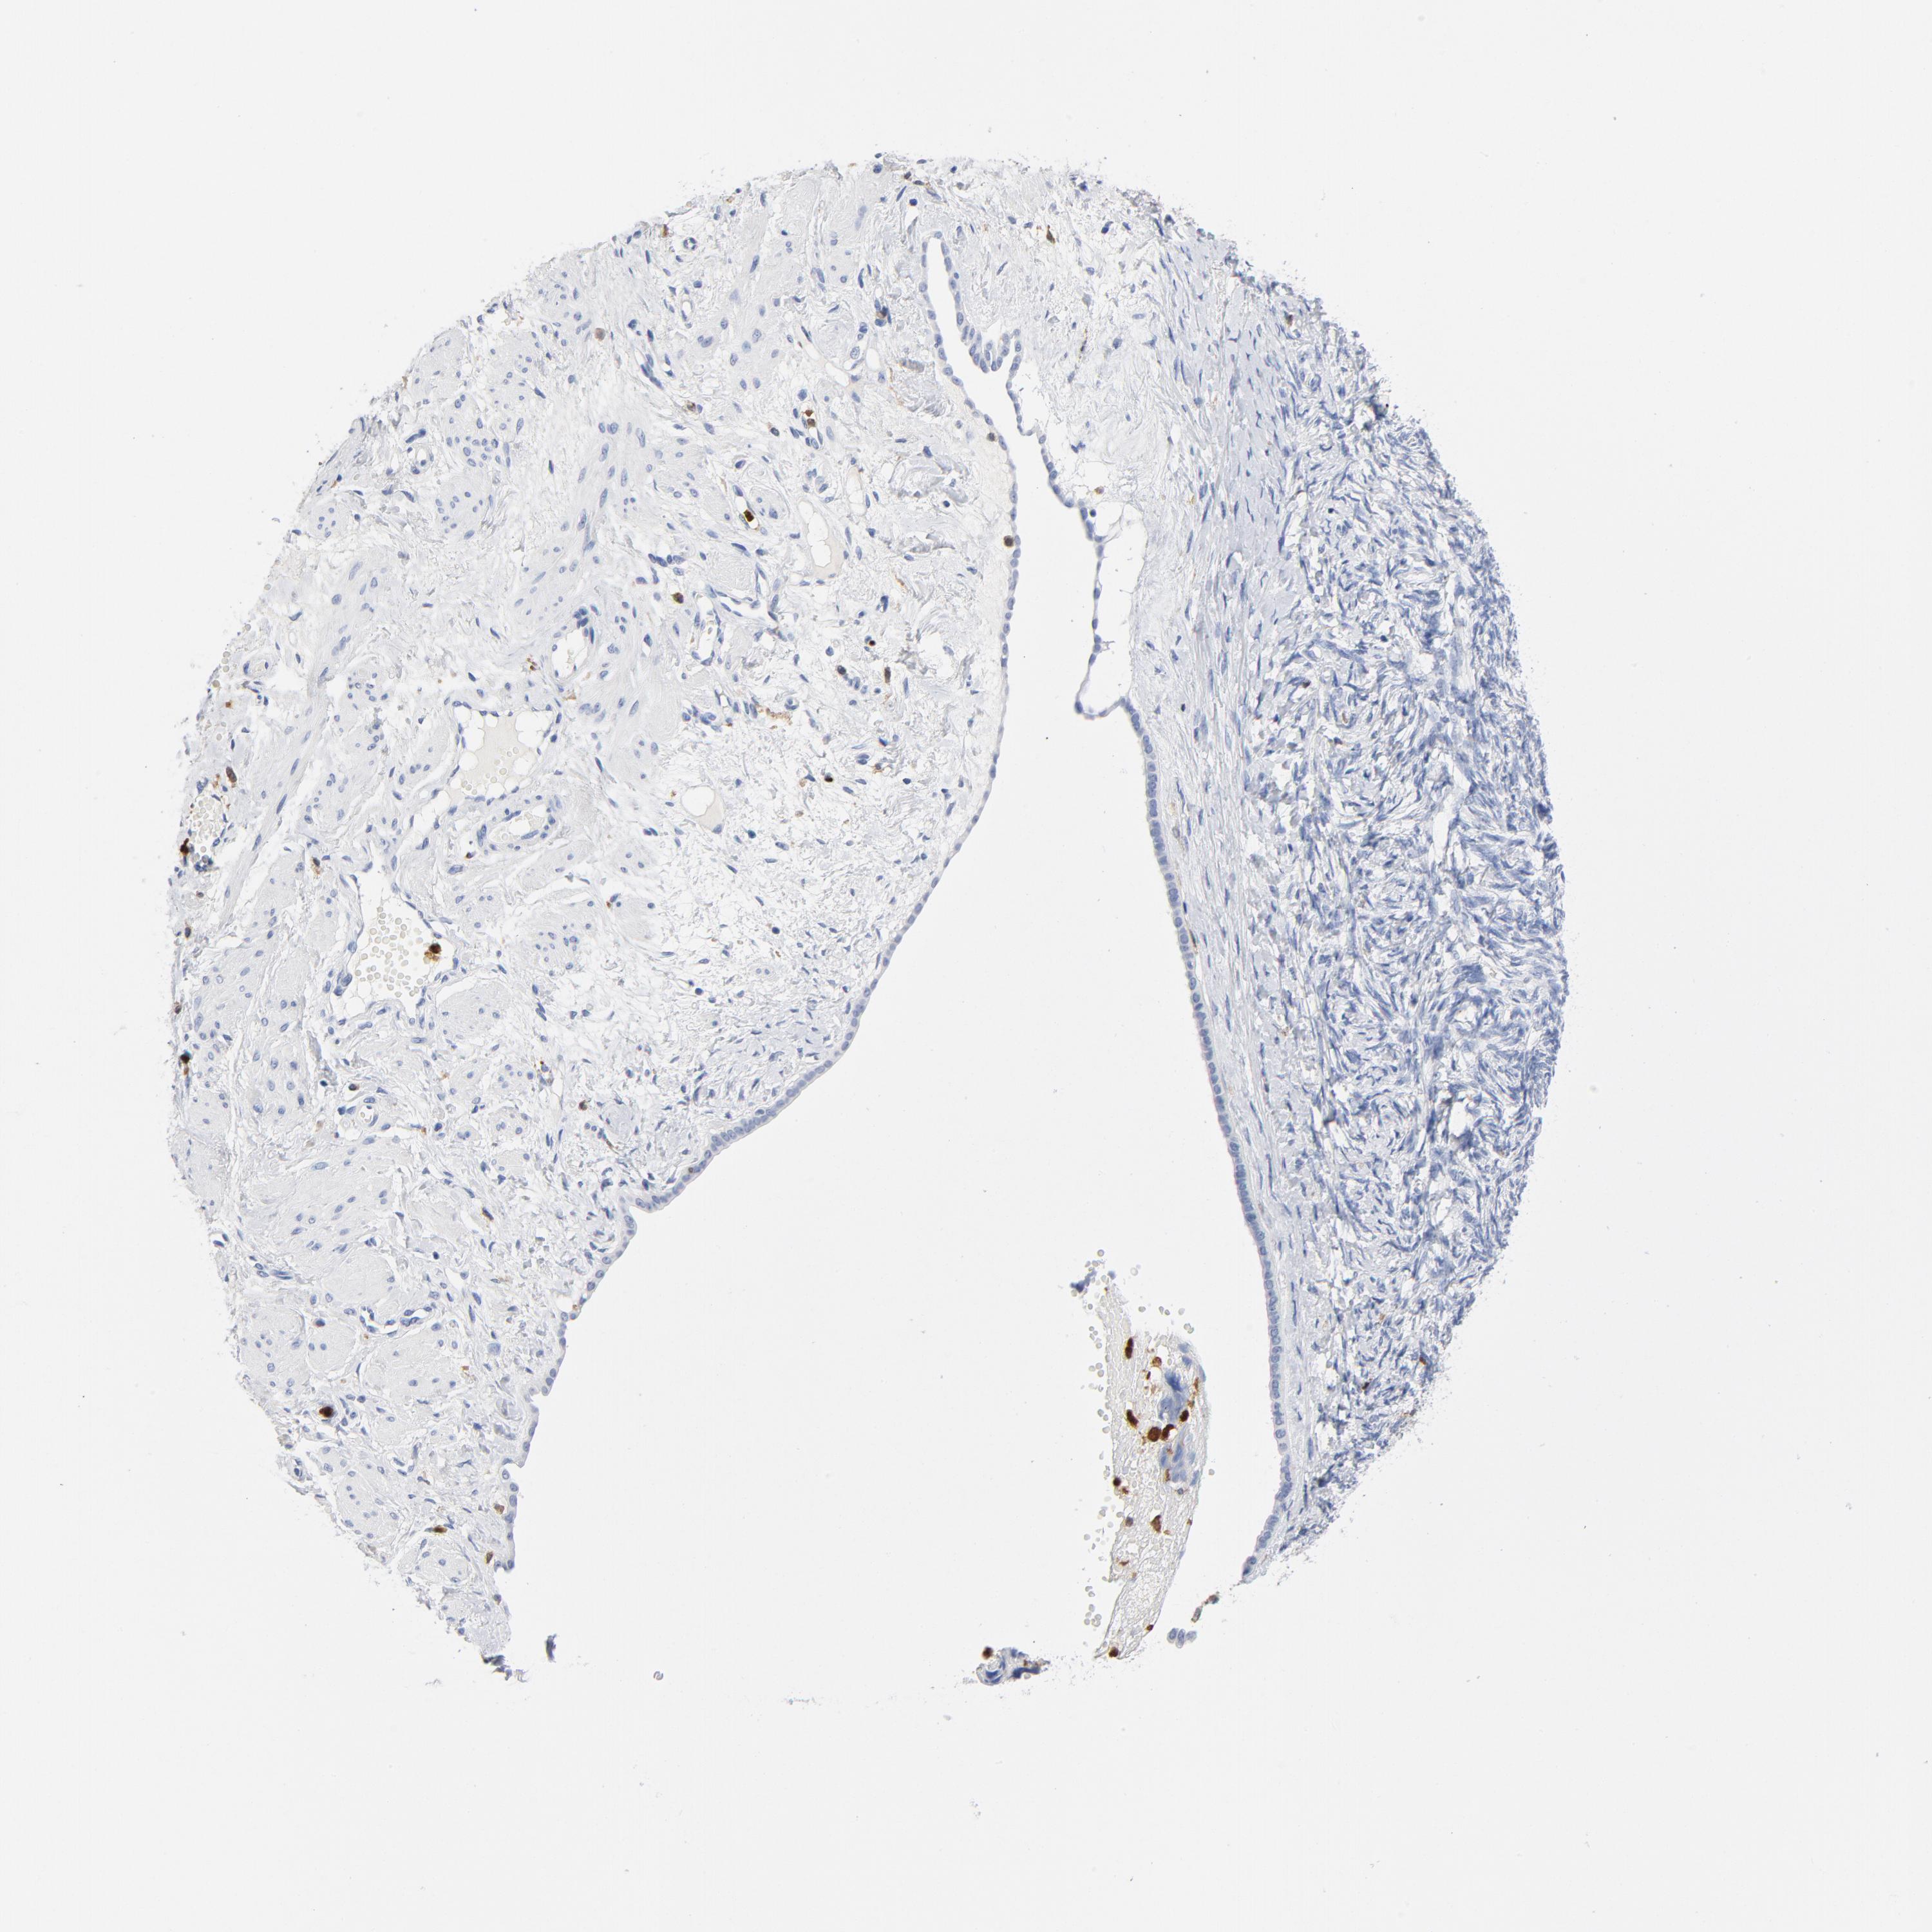

OVARIAN CANCER - Protein expressioni

A mouse-over function shows sample information and annotation data. Click on an image to view it in a full screen mode. Samples can be filtered based on level of antibody staining by selecting one or several of the following categories: high, medium, low and not detected. The assay and annotation is described here.

Note that samples used for immunohistochemistry by the Human Protein Atlas do not correspond to samples in the TCGA dataset.

Antibody stainingi

Antibody staining in the annotated cell types in the current human tissue is reported as not detected, low, medium, or high, based on conventional immunohistochemistry profiling in selected tissues. This score is based on the combination of the staining intensity and fraction of stained cells.

Each image is clickable and will lead to virtual microscopy that enables deeper exploration of all samples and also displays staining intensity scores, fraction scores and subcellular localization as well as patient and tissue information for each sample.

Antibody HPA047836

Antibody HPA052095

Antibody CAB004524

Staining

High

Medium

Low

Not detected